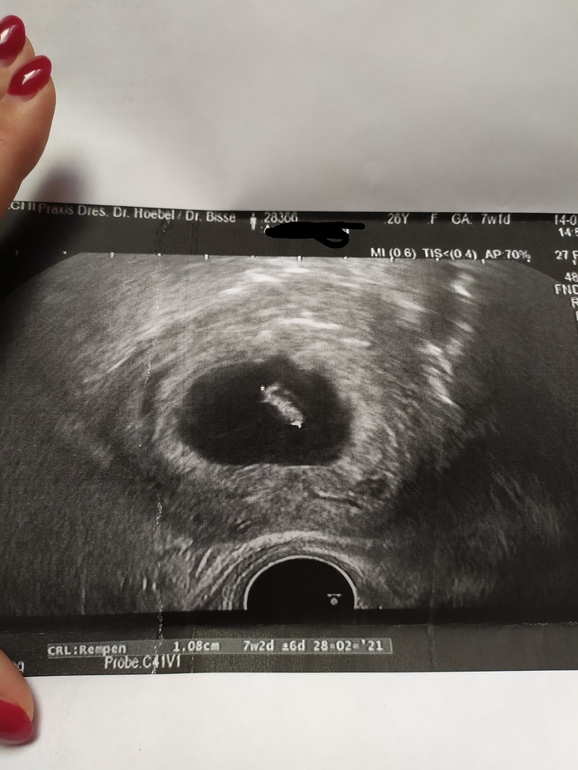

Юлия *

Полных 7 недель отлично видно. Вот наше фото было в 7 нед. Есть что разглядеть)

мне как после УЗИ выдали фотку, сразу своему сказала, что девочка похоже опять)